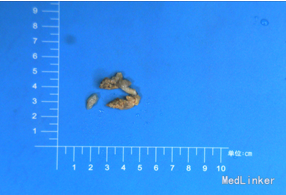

诊断 处理

完善相关检查,在气管插管麻下行“左额眶部占位病变切除术”。术后病理诊断为“(左眼眶)丛状神经纤维瘤”。术后给予患儿脱水、营养脑神经、抗感染等对症治疗。复查CT未见明显异常。